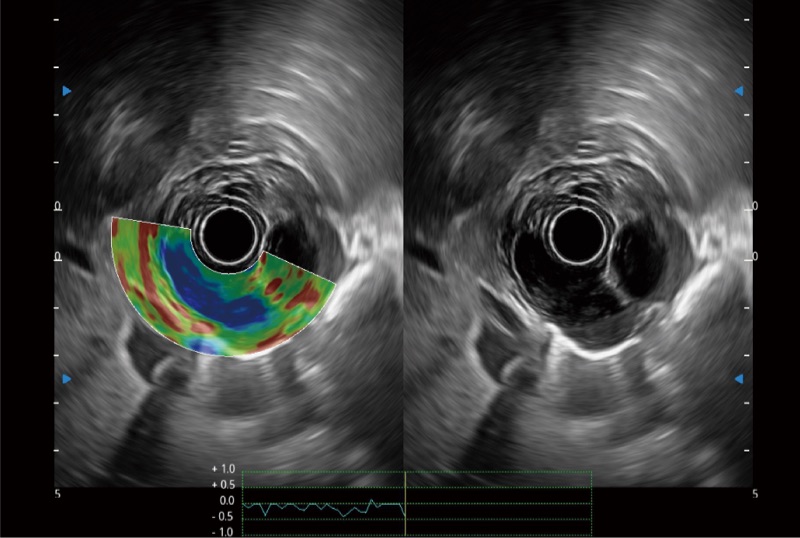

可人为将灰阶图像转变成彩色的显示方式,增强人眼对于不同回声强度的敏感度,主观上增加了图像分辨率

微米成像技术提升了对组织斑点噪声信号的抑制能力,并进一步强化边界信息,从而获得信噪比更优、边界更清楚锐利的图像

随着组织深度的变化,超声接收频率进行智能匹配跟踪,确保图像中、远场良好的穿透力以及整场一致的分辨力,从而得到均一的画质